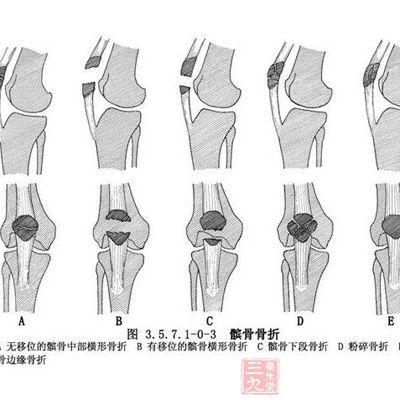

髌骨骨痂生长过程图,髌骨骨裂

髌骨骨折的原因 为什么会患上髌骨骨折

髌骨骨折图片

髌骨骨折x线图片

髌骨骨折

髌骨图

髌骨图片